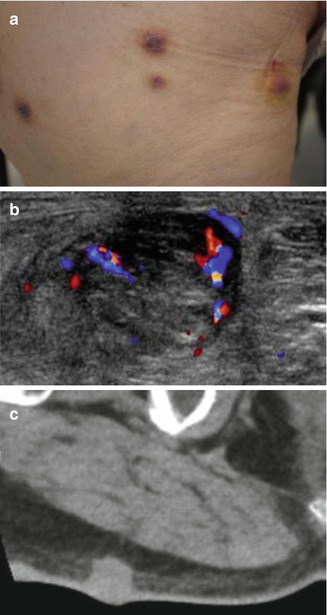

Angiosarcoma in a 70-year-old men. (a) Clinical photograph. (b) Axial color Doppler image. (c) Computed tomography. (a) Clinical appearance of numerous skin lesions. (b) Ultrasound with color Doppler shows nodular superficial tissue mass, slightly hypoechogenic and predominately peripheral flow within the soft tissue mass. (c) Computed tomography demonstrates a non specific subcutaneous nodular lesion